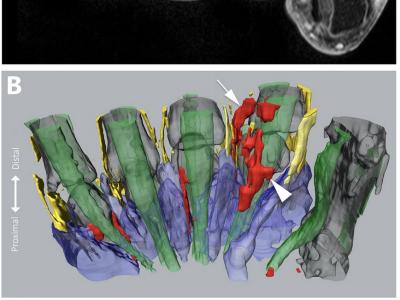

Interosseous tendon inflammation (ITI) the new predictor of clinical RA in pts w/ clinically suspect arthralgia. 600+ pts Hands MRI Present 10% pts w/ CSA, 1% symptom free 27% ACPA+ 7% ACPA- HR 4.5 dvlpmt of clinical RA https://t.co/BmRF1tLFx9 Abs#2204 #ACR22 @RheumNow https://t.co/F8DUxiI2dh